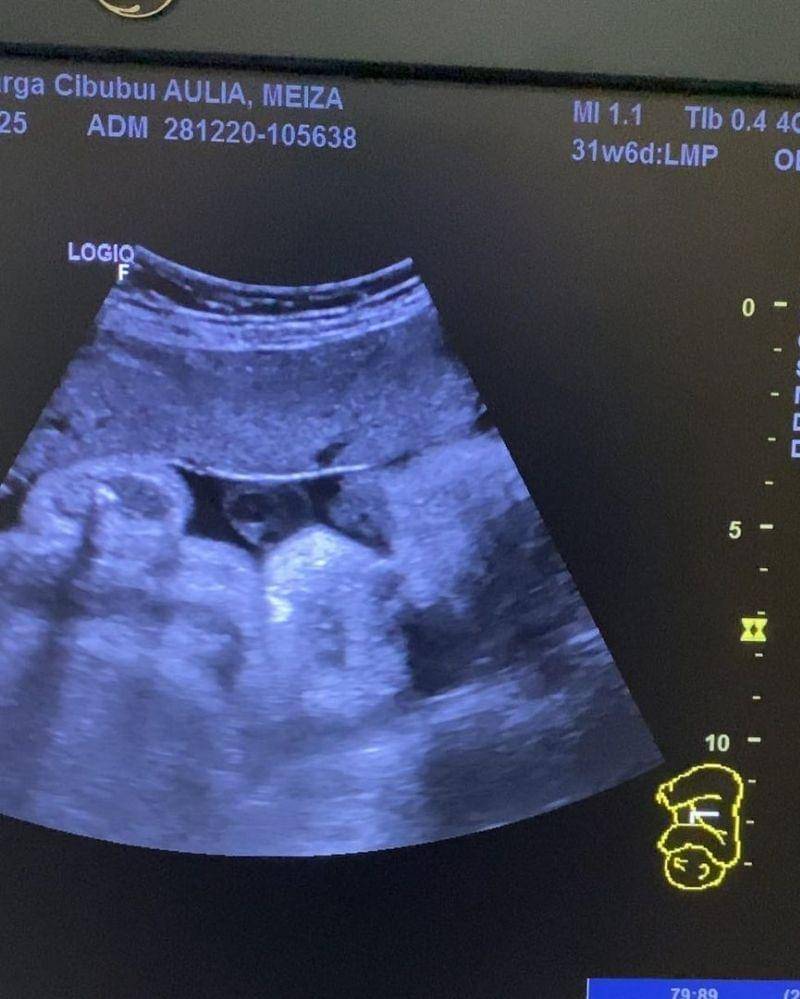

18. Khan Gionino, putra Meiza Aulia Coritha dan Eza Gionino

Selanjutnya ada foto USG kehamilan Meiza Aulia Coritha, istri dari pesinetron Eza Gionino. Saat itu Meiza sedang mengandung putra keduanya yang kini diberi nama Khan Gionino.

Pada 21 Februari lalu, Meiza akhirnya melahirkan putra keduanya tersebut dan kini telah berusia 1 tahun. Tak lama lagi Khan juga akan menjadi seorang kakak lho, Ma.